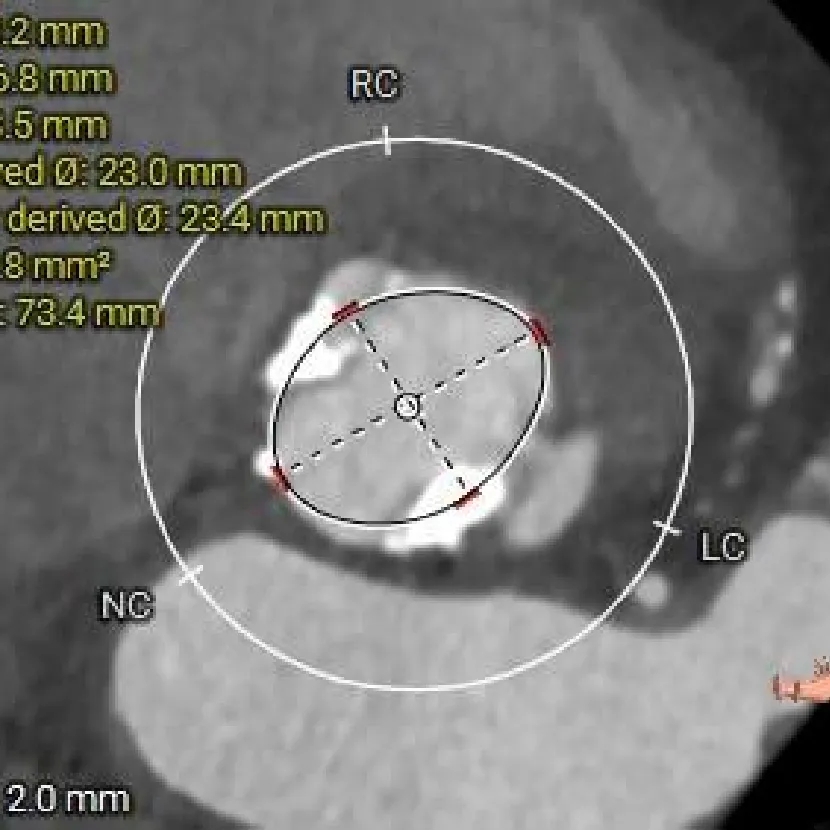

瓣上结构测量

瓣上2mm

23.4mm